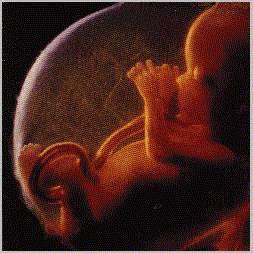

الشهر الثالث: من بداية الاسبوع الحادي عشر حتى نهاية الاسبوع الثالث عشر العضو التناسلي للجنين: في الشهر الثالث لايكون العضو التناسلي الخارجي للجنين قد تشكل بعد. الجنين يتحرك! انه يتحرك فعلا,ولكنك لاتشعرين بحركته لانها ضعيفه جدا. اكثري من شرب السوائل: وذلك لمساعدة كليتك في عملهما الاضافي لطرد فضلات الجنين.والاكثار من شرب السوائل(حوالي لتر ونصف الى لترين) يجنبك التهابات البول التي غالبا ماتصيب الحوامل علامات التهاب البول: الاحساس ببعض الحرقة في بداية التبول رغبه متكرره في النهار كما في الليل مع حريق شديد اثناء خروج البول عواقب عدم معالجه الالتهاب في البول: بالنسبه للام:يمكن ان يطاول الالتهاب كليتيها بالنسبه للجنين: يمكن ان يؤدي الي وقف نموه احتما حدوث اجهاض او ولادة مبكره الوقايه من التهاب البول: الاكثار من شرب الماء الاستراحه في جو دافئ وتجنب الرطوبه والبرد حياتك الجنسيه اثناء الحمل: قد لاتشعرين برغبة جنسيه في بداية الحمل,بسبب التغيير الكبير الذي طرا على جسمك من الناحية الهرمونيه .في هذه الحاله عليك بمصارحة الزوج من دون خجل فضلا عن ممارسه بلا رغبه من باب الواجب.لانه هذه الممارسه على هذا النحو تفقدك الرغبه فيه حتى بعد الولادة اذ ينشأ لديك نوع من ردة الفعل المرتبط بعدم اللذه! والاستعاضه عنها بالمداعبات اللطيفه التي توفر لكما المتعه الضروريه لحياه زوجيه سليمه ومشتركه علامات الالتهاب التناسلي: افرازات مهبليه كثيره عن المعتاد واكثر سماكه وذات رائحه كريهه الاحساس بحكه في منطقة الفرج الاحساس بألم اثناء العلاقة الجنسيه عواقب الالتهاب التناسلي: ينبغي عدم اهمال اي نوع من الاتهابات واذا عولج في الوقت المناسب فانه لايترك اثراً ام اذا اهمل فيؤدي الى: اجهاض ولادة مبكره اذا حدث في الشهور الاخيره من الحمل اصابة الام بالتهاب حاد لحظة الولادة يمكن ان يؤدي لاحقا الي التهاب مزمن في الرحم اصابة الطفل بالتهاب عند الولاده عدم بروز حلمة الثدي: اذا لم تكن حلمة الثدي بارزه . شديهما قليلا لجعلها بارزه وقابلة للمص. يتبع:26:الشهر الثالث: من بداية الاسبوع الحادي عشر حتى نهاية الاسبوع الثالث عشر العضو التناسلي...